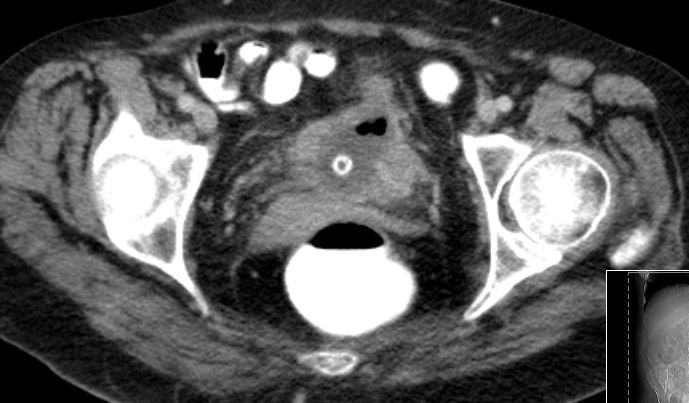

| SCC | 54-jährige geistig behinderte Frau mit einem

Plattenepithelkarzinom der Harnblase. Radikale Zystektomie und Anlage eines

Ileumconduits. Histologisch Infiltration des perivesikalen Fettgewebes. 8 Monate

später Rezidiv an der linken Beckenwand mit Beckenknocheninfiltration.![]() | |||